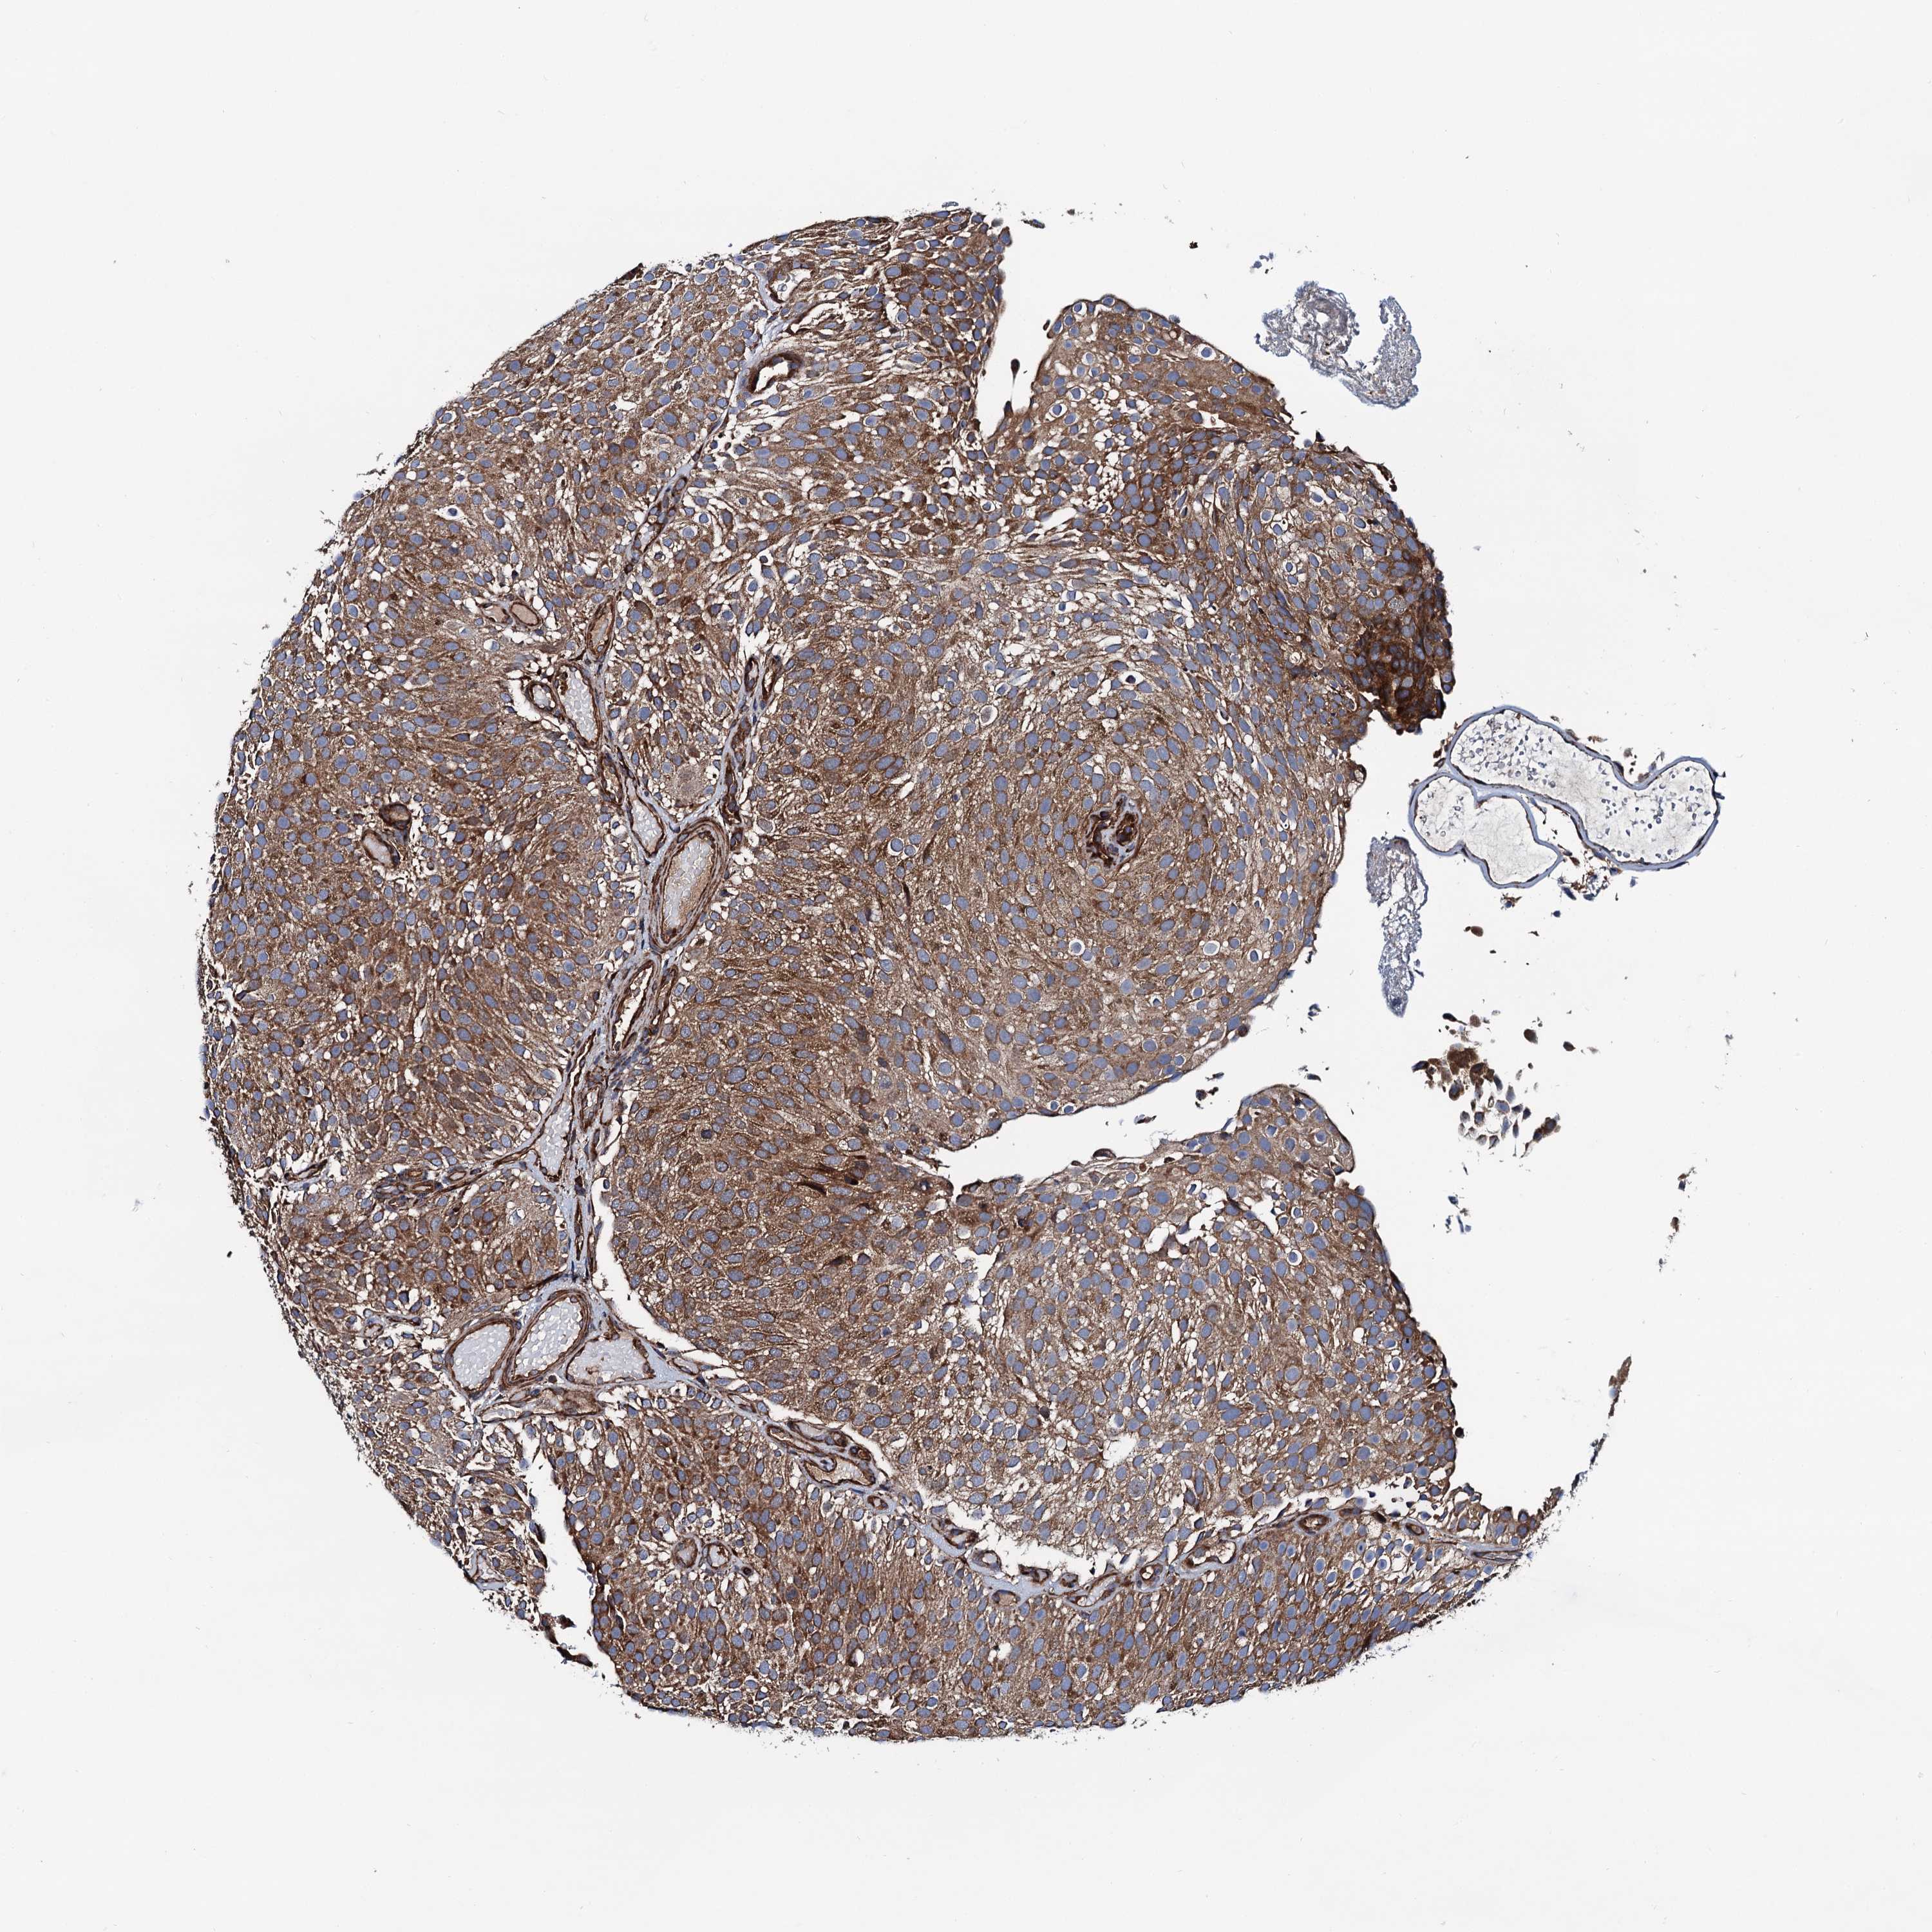

UROTHELIAL CANCER - Protein expressioni

A mouse-over function shows sample information and annotation data. Click on an image to view it in a full screen mode. Samples can be filtered based on level of antibody staining by selecting one or several of the following categories: high, medium, low and not detected. The assay and annotation is described here.

Note that samples used for immunohistochemistry by the Human Protein Atlas do not correspond to samples in the TCGA dataset.

Antibody stainingi

Antibody staining in the annotated cell types in the current human tissue is reported as not detected, low, medium, or high, based on conventional immunohistochemistry profiling in selected tissues. This score is based on the combination of the staining intensity and fraction of stained cells.

Each image is clickable and will lead to virtual microscopy that enables deeper exploration of all samples and also displays staining intensity scores, fraction scores and subcellular localization as well as patient and tissue information for each sample.

Antibody HPA020873

Antibody HPA040413

Staining

High

Medium

Low

Not detected

Intensity

Strong

Moderate

Weak

Negative

Quantity

>75%

75%-25%

<25%

None

Location

Nuclear

Cytoplasmic/membranous

Cytoplasmic/membranous,nuclear

Urothelial carcinoma, High grade

Urothelial carcinoma, Low grade

Urothelial carcinoma, NOS